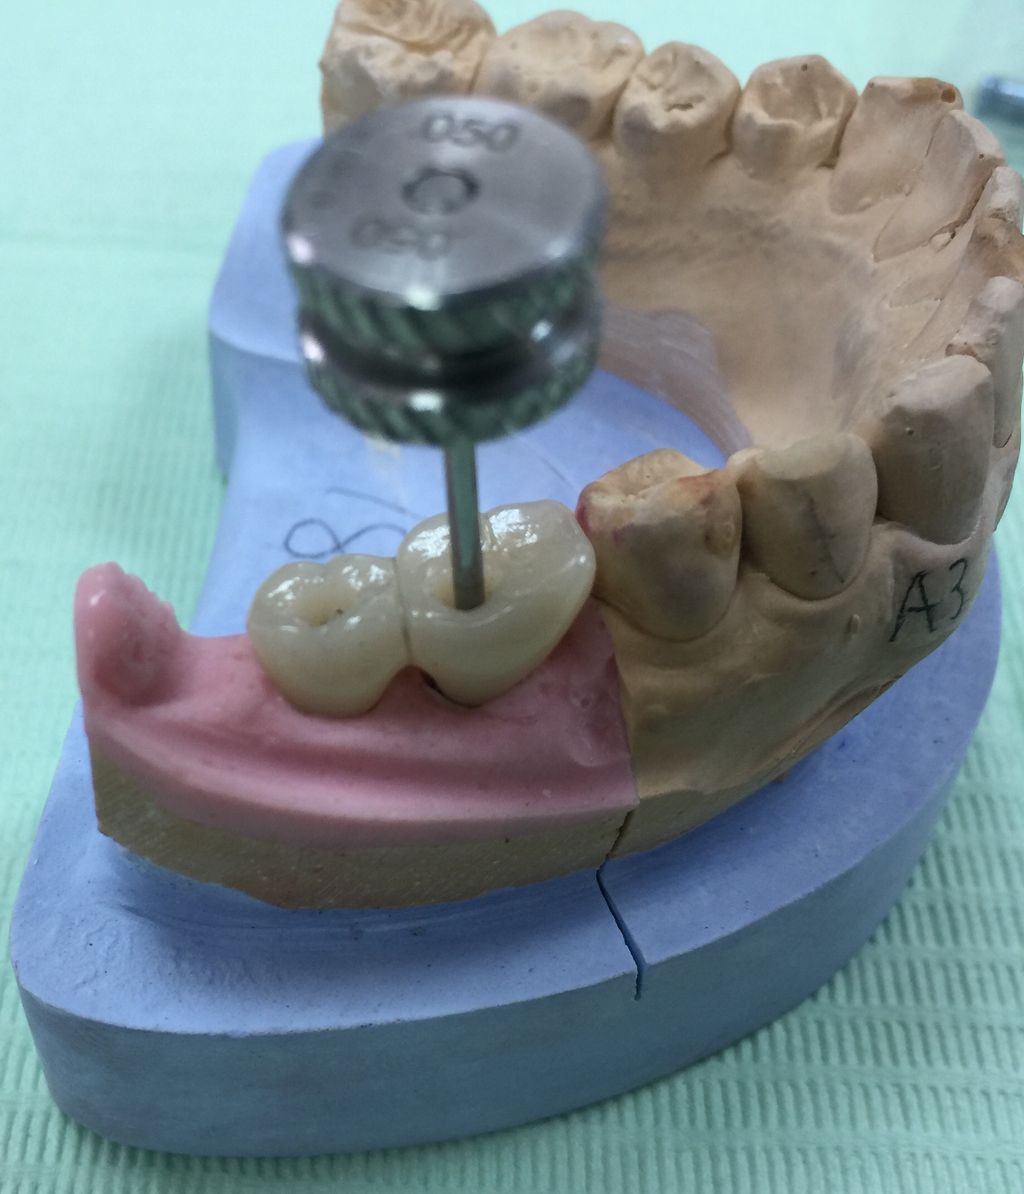

技工士さんが、コレをもとに全てがセラミックでできた被せ物を作ってくれます。

これをネジを使ってインプラントに接続します。